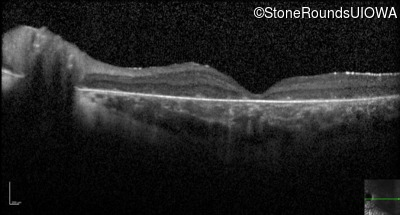

Optical Coherence Tomography - Right - 10/400 sc

Exemplar / OCT Stack

OCT Stack